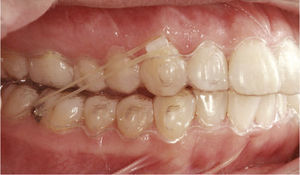

Corrección de mordida cruzadaLas mordidas cruzadas se pueden tratar con el sistema Invisalign de forma muy predecible. La corrección de la mordida cruzada posterior se puede llevar a cabo con el sistema Invisalign exclusivamente o bien combinándolo con un tratamiento previo con botones y elásticos entrecruzados. La figura 11a muestra una oclusión clase II con mordida cruzada de los dientes 16 y 46. El tratamiento con Invisalign incluyó la distalización en la arcada superior derecha con corrección de la mordida cruzada mediante expansión transversal en la región del 16. La figura 11b muestra la situación intraoral a la finalización del tratamiento con configuración de una relación clase I y de una oclusión funcional de la región molar.